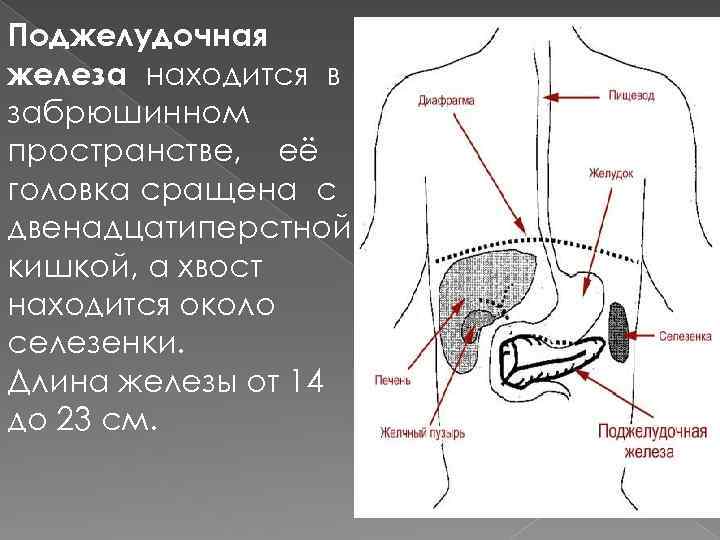

Поджелудочная железа находится в забрюшинном пространстве, её головка сращена с двенадцатиперстной кишкой, а хвост находится около селезенки. Длина железы от 14 до 23 см.

Поджелудочная железа находится в забрюшинном пространстве, её головка сращена с двенадцатиперстной кишкой, а хвост находится около селезенки. Длина железы от 14 до 23 см.